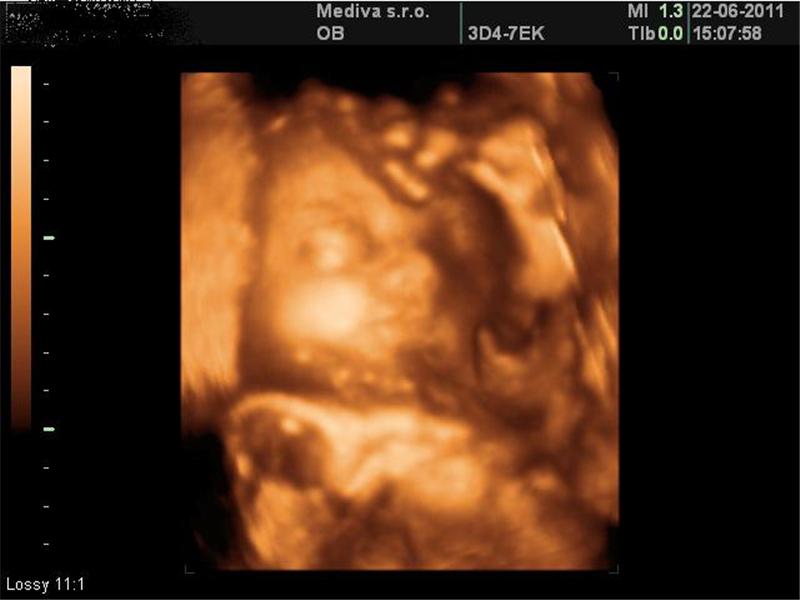

Ultrazvuky

3 fotografií